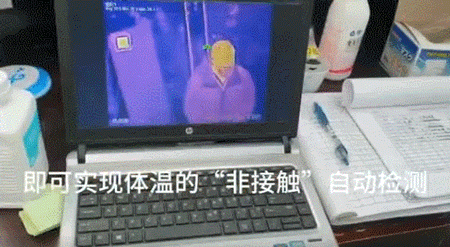

AI体温检测和影像识别

疫情期间,没带口罩不准外出

而测温也成了家常便饭

尤其是在医院、火车站、机场等

人群密集的区域,测温更是必要

为了应对医院患者的

就诊发热工作和返程客流高峰

我们的5G技术也派上了用场

许多地区都在医院和火车站用了

5G热力成像测温系统

通过红外线体温检测摄像头

5G无线接入设备、体感黑体等高科技

在无接触的情况下,能在1-10米范围内

秒速检测出人的体温

如果被检测的人体温有异常

或有疑似的发烧症状

该设备就会发出提示

及时提醒工作人员

这样检测体温不仅高效

还能避免检测者与被检测者

之间的交叉感染

测温安检一体机

上海地铁2号线还启用了

全程无接触的测温安检一体机

将红外测温设备与太赫兹人体安检仪结合

人只要经过此设备

就能同时被安检和测温

由于疫情爆发在春节,如今回家过年的人们陆续返程,大批人流出现在机场、火车站等地,在这种情况下,传统体温监测难以实现高效筛查。

为解决这一问题,百度AI多人体温快速检测解决方案应运而生。

该技术基于人脸关键点检测及图像红外温度点阵温度分析算法,可以对一定面积内乘客的额头温度进行检测,即便是佩戴帽子和口罩也能够快速筛查。

1分钟内可以实现逾200人同时通过单通道,实现体温检测,乘客几乎不用停留,避免了人员拥挤,且温度识别误仅差在±0.3℃。

如此非接触式的测温方式,大大降低了交叉感染的风险。